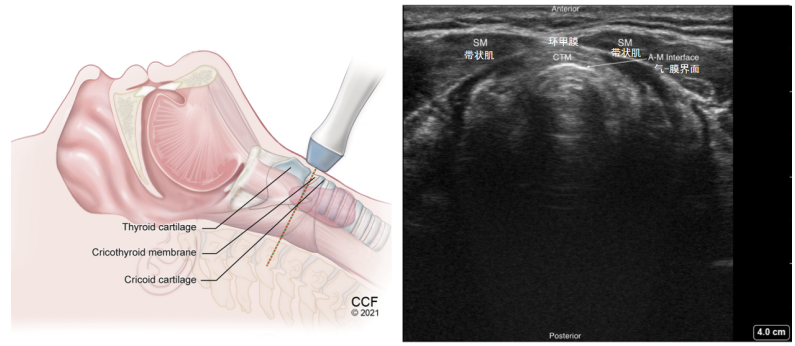

(3)环甲膜横切面(图11):探头继续下滑会看到一个密度高于软骨的结构,位于甲状软骨与环状软骨之间。

图片

图11  环甲膜横切面